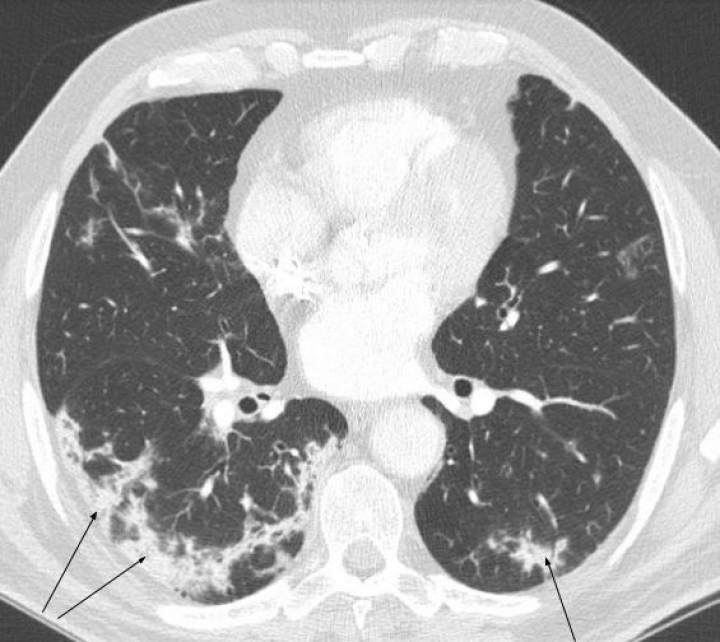

Este virus-RNA pertenece al nuevo coronavirus del género ß, uno de los pocos capaces de infectar a humanos. Entre las manifestaciones más graves de la enfermedad, la neumonía recuerda a la del síndrome respiratorio agudo severo (SARS) y a la del síndrome respiratorio de oriente medio (MERS). Sin embargo, aunque su contenido genómico es común para todos los coronavirus, su genoma es diferente al de ambos, SARS-CoV y MERS-Cov; y por tanto, el virus, entre cuyos factores de riesgo habría que destacar la edad avanzada y las comorbilidades de tipo cardiovascular, tiene diferentes presentaciones clínicas y también distintos hallazgos pulmonares en las pruebas de imagen (radiografías y tomografía computarizada; figura 1).